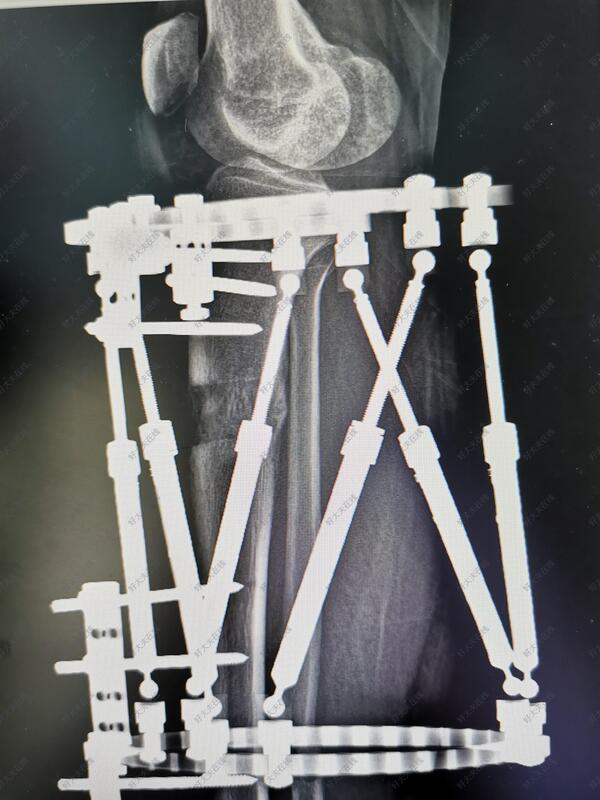

治疗后

- 治疗后90天

术后2月可以去上班,现在拆除部分外固定针实现动力化

- 治疗后30天

正在恢复中!期待不久的将来健步如飞